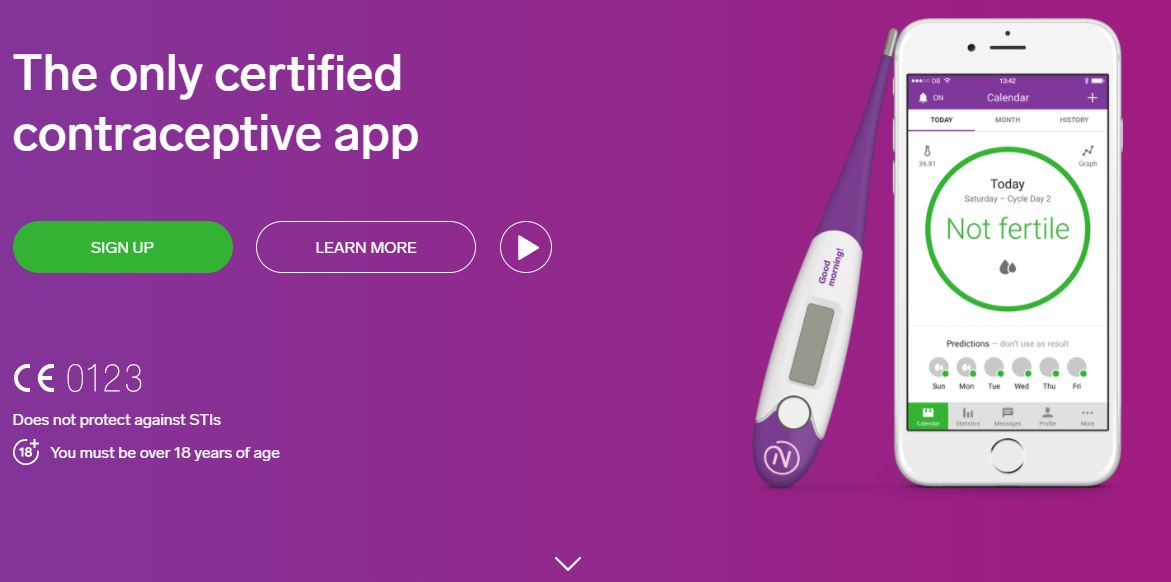

Si tratta di un’applicazione certificata come dispositivo medico in Europa, ad oggi utilizzata da oltre 500 mila persone. Scaricabile su ogni dispositivo mobile in modo gratuito per il primo mese, “Natural Cycles” ha un costo di 65 euro all’anno con termometro annesso.

Come funziona?

È semplice: la donna deve effettuare una misurazione quotidiana della temperatura corporea e un algoritmo poi s occupa di analizzare il ciclo mestruale. Occhio al colore che indica la fertilità: se è rosso vi è un’alta possibilità di rimanere incinte, mentre se è verde si possono avere rapporti senza alcun pericolo di gravidanza. L’applicazione però non protegge da malattie sessualmente trasmissibili.